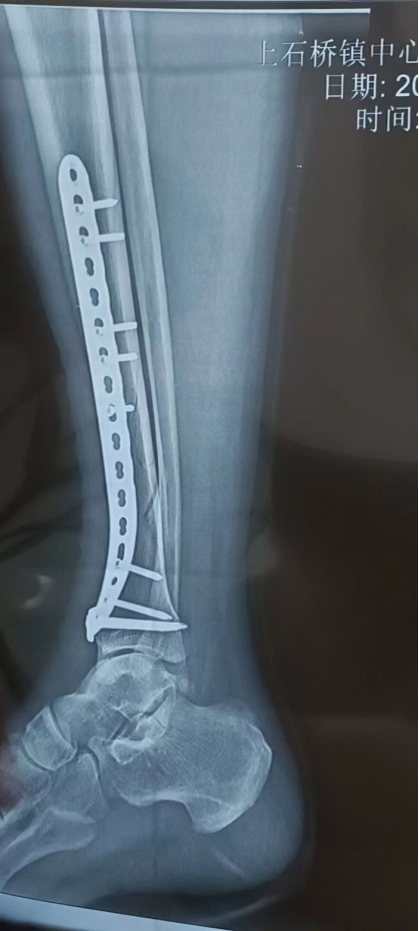

在综合考虑患者的身体状况与患者本人意愿后,决定为患者实施手术治疗。在李方辉副主任指导下,该患者于2月8日下午17:02在腰椎麻醉下行右胫骨骨折切开复位内固定术,手术过程十分顺利,术中已解剖复位。术后复查提示骨折端已复位,对位对线良好,内固定稳定,患者对手术效果非常满意。